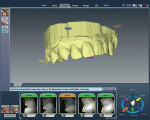

The Restorative Technique

On the preparation day, the patient presented with the fragment from tooth No. 7 still successfully bonded in place. The maxillary anterior teeth were scanned as “clones” intraorally using the E4D Dentist. The scan was verified on the computer and appeared to have stitched together accurately (Figure 5). The maxillary right lateral incisor was then prepared for a full-ceramic crown with deep chamfer/shoulder margins to allow for a full 2 mm of ceramic thickness. A slightly more aggressive preparation was done to prevent the restoration’s color from becoming compromised if the tooth stump became discolored over time as a result of the traumatic incident. Retraction around tooth No. 7 was achieved with a double retraction cord technique, allowing the anterior maxillary teeth and preparation to be scanned intraorally (Figure 6). A single-tooth bite registration was made and scanned intraorally as well. Using E4D’s CAD software, a detailed proposal was generated based on the scanned preoperative clone. The design proposal was refined using the CAD software and the bite was verified using the scanned bite registration (Figure 7). An e.max Low Translucency (LT) ceramic block was chosen and the block shades were narrowed down to A1and B1. In this case, both shades of blocks were milled to clinically compare colors and achieve the closest base color match possible. Both milled restorations were tried in the mouth prior to crystallization to ensure proper fit, contacts, occlusion, and contour. Using the mapping of characteristics, contours were refined with high- and low-speed diamond burs. After complete seating of the restoration, symmetry of shape (between teeth Nos. 7 and 10) was achieved. Interproximal embrasures, contacts, and prominent facial convexities/concavities (primary facial anatomy) were refined. Next, subtle depressions, constrictions, and angles (secondary facial anatomy) were developed. Finally, vertical and horizontal striations as well as roughness, dimpling, and minor incisal discrepancies (tertiary anatomy) were added. While intricate sounding, these post-milling adjustments took less than 5 minutes to achieve.